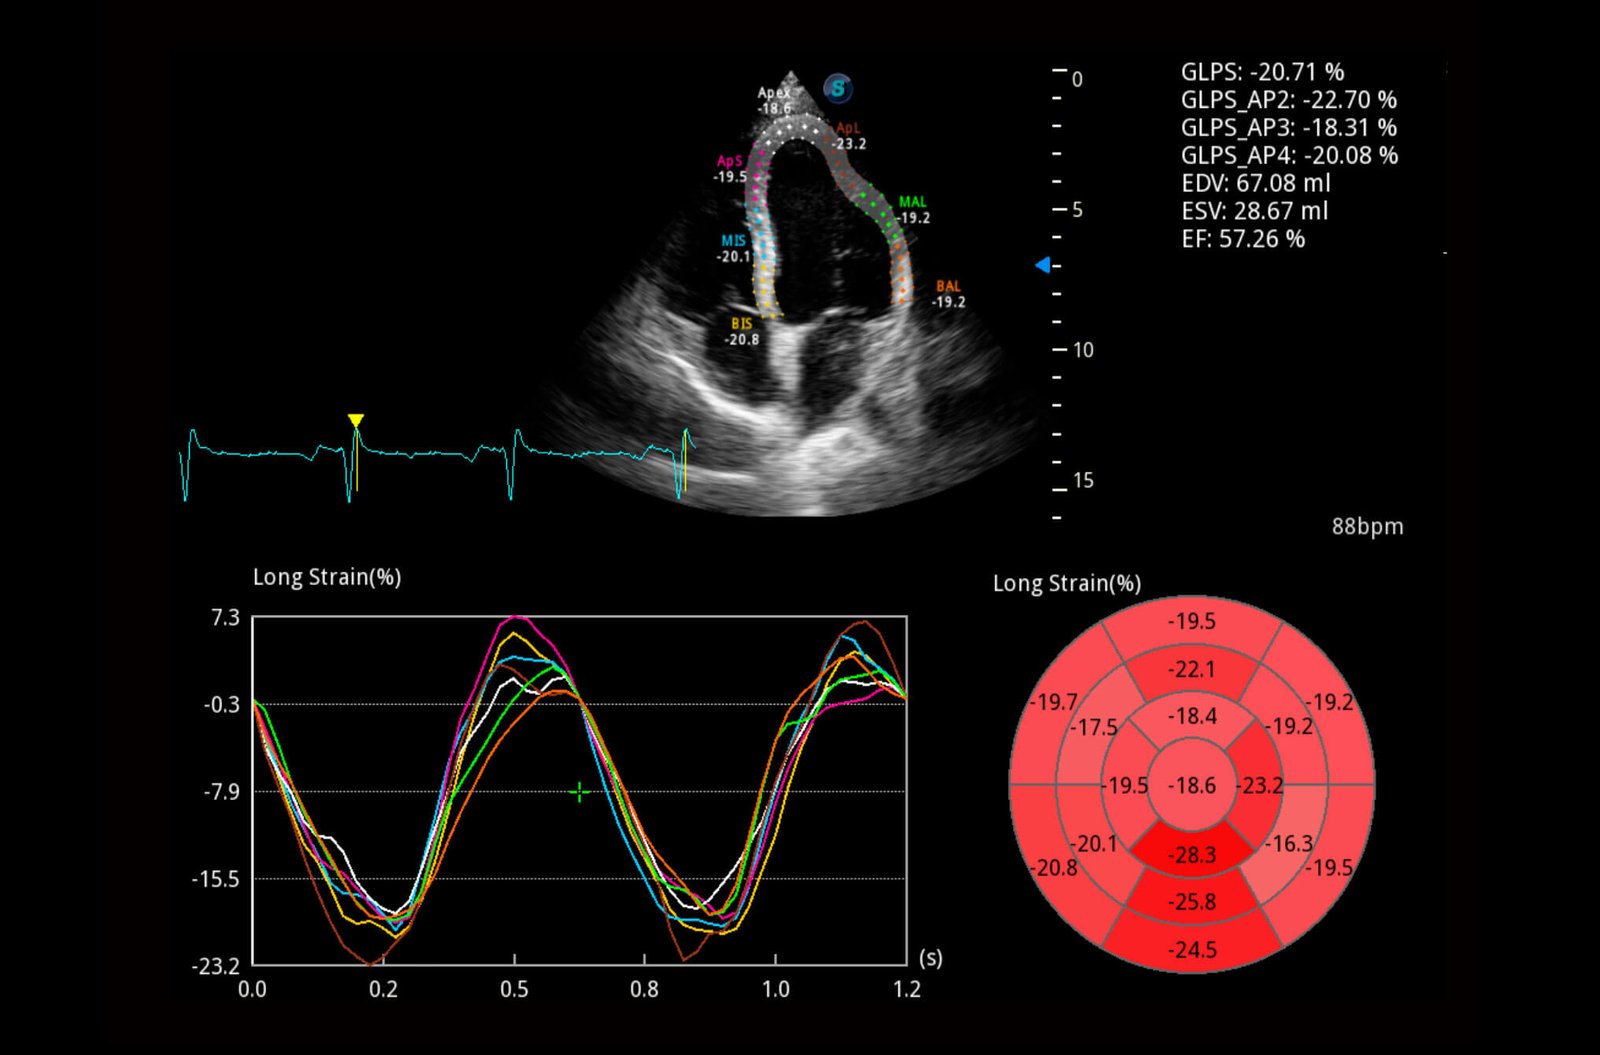

Single Crystal Sector S1-5

Innovative single crystal material effectively enhances energy transmission and elevates spatial resolution for better clarity, mainly for cardiology and transcranial applications.